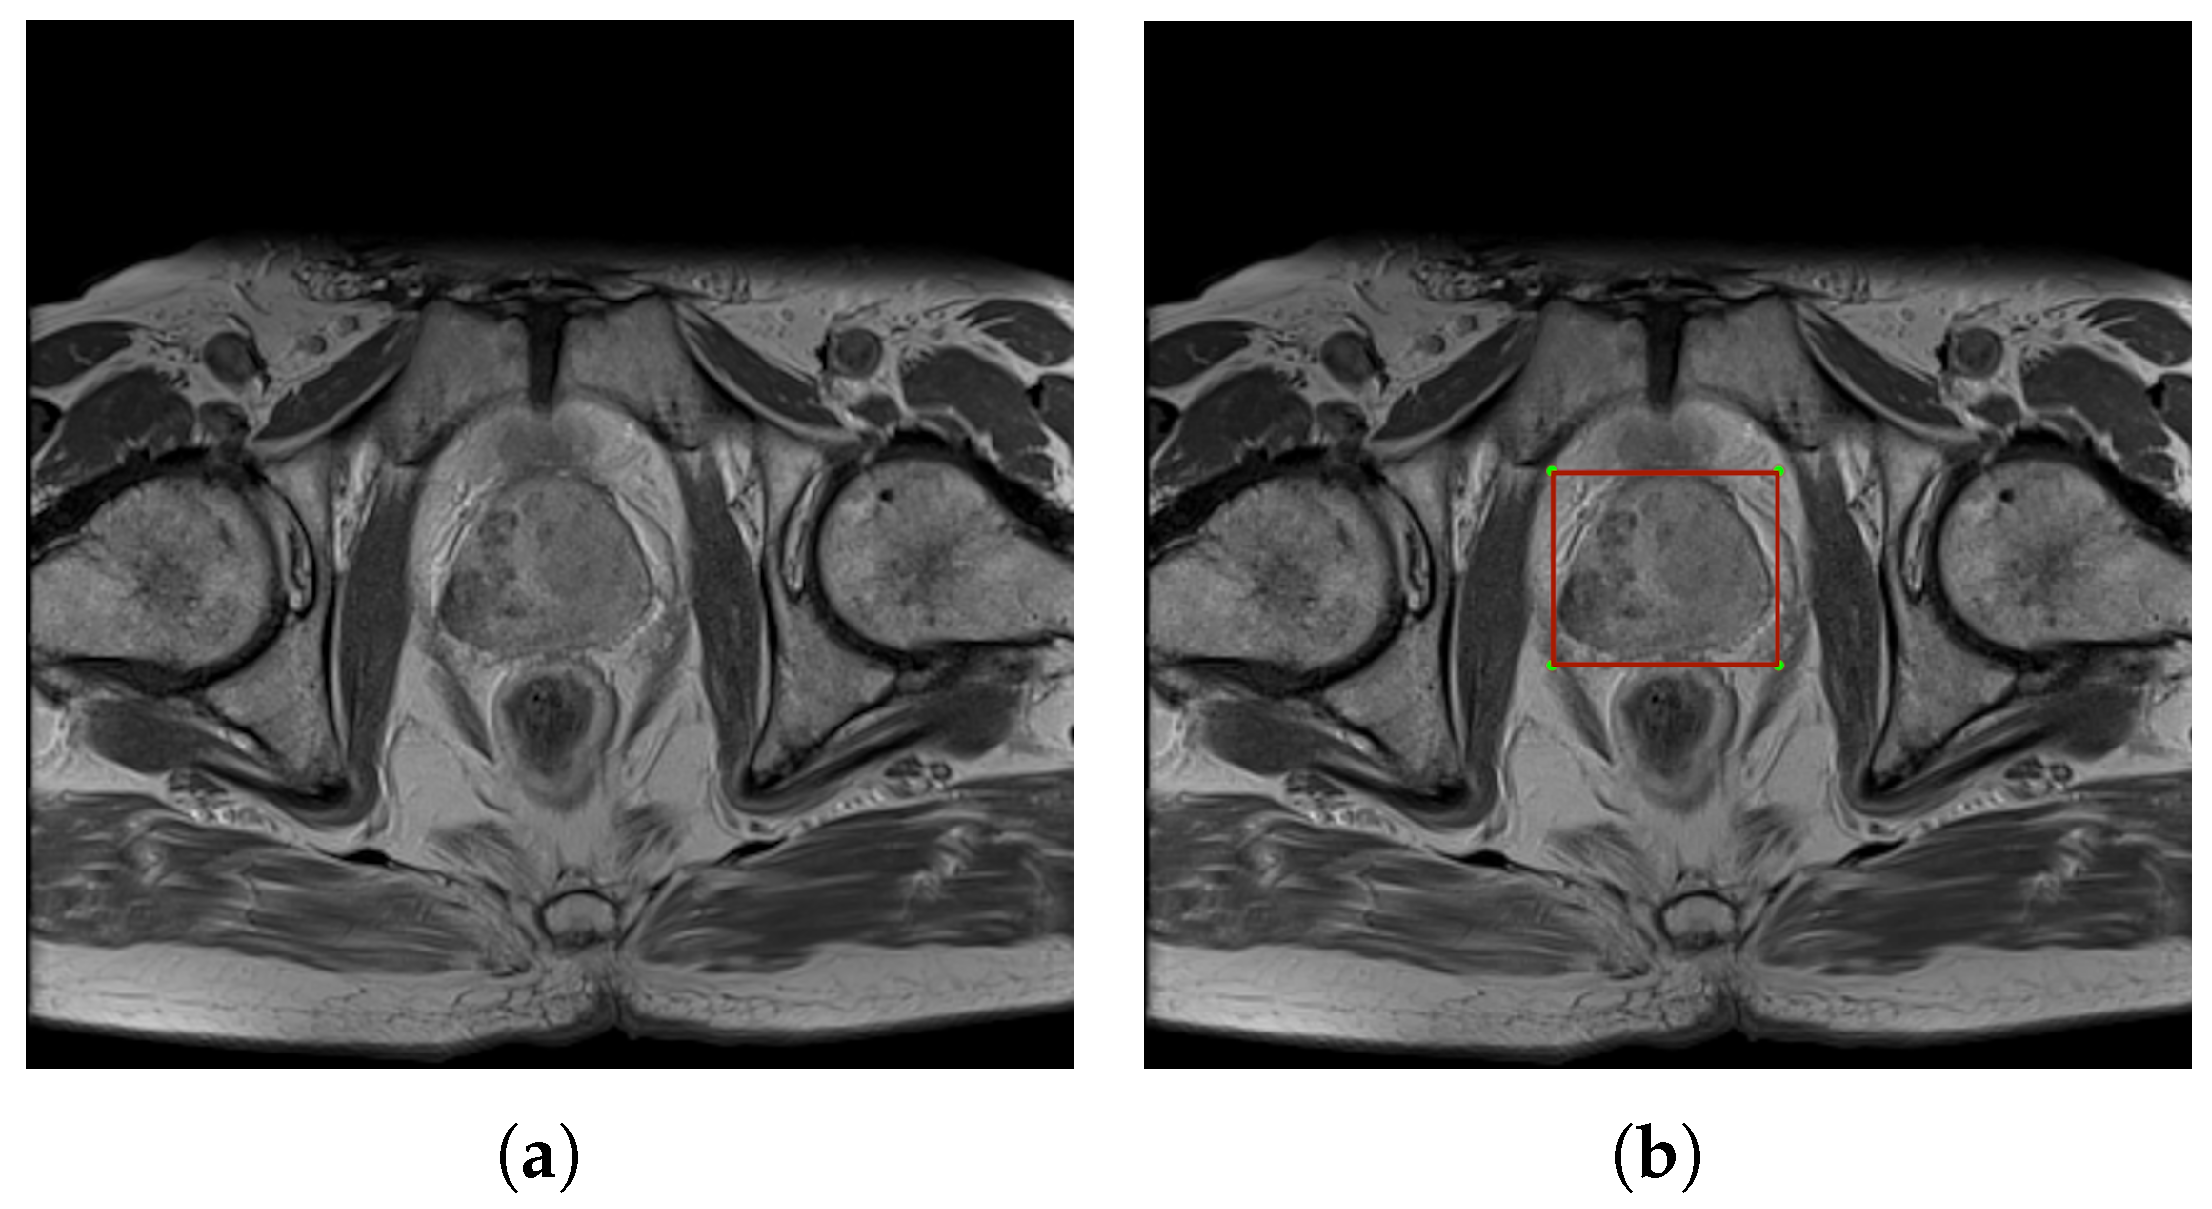

To train the YOLOv4 network, images of any size with three color channels in PNG and extracted labels in TXT were utilized. The TXT file contains information about the classes of the marked object in numerical form and the object bounding box related to the original image. An example with the detected prostate organ area is presented in Figure 2.

Figure 2.

Images illustrate (a) an exemplary MRI slice and (b) the same slice with a marked prostate bounding box. Images are utilized as training data for YOLOv4.